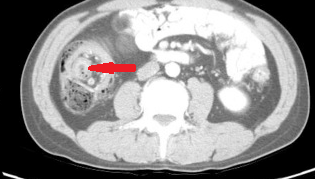

Σχήμα 1 . Η αξονική τομογραφία με ενισχυμένη με σκιαγραφικό έδειξε μια ακανόνιστη περιφερική μάζα στο αριστερό μισό του εγκάρσιου κόλου με λιπώδη συσσωμάτωση δίπλα σε παχυσμένο τοίχωμα του εντέρου. ( Ευγενική παραχώρηση Δρ. Β. Πενόπουλος ) .